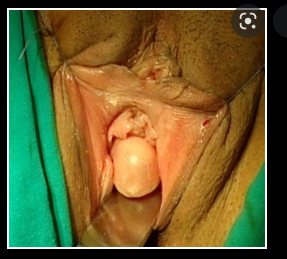

bartholin gland cyst

A

• secrete muscus and lubricat the vagina

• empty into 4 and 8 ocolock ducts of the vaginal vestibule

distal to hymenal ring